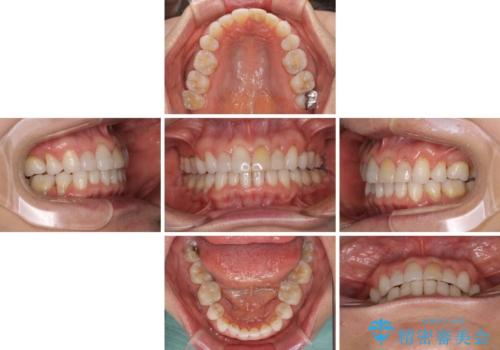

矯正治療の後戻り インビザライン・ライトでの再矯正

- 上下前歯を中心に、以前行った矯正治療の後戻りが気になるとのことで来院された患者様です。

後戻りは軽度であったため、インビザライン・ライトにて治療を行うこととしました。

矯正治療後は、再度後戻りすることを極力回避するために、下顎前歯の舌側を細いワイヤーを用いて保定することとしました。